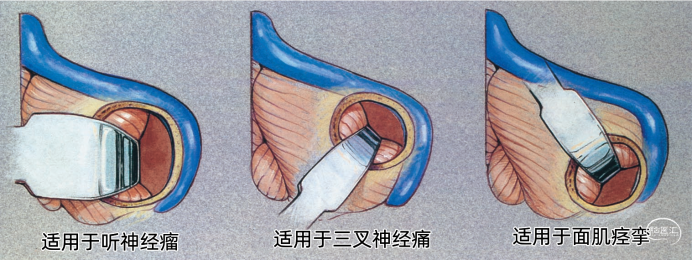

▼15.小脑绒球下入路

小脑绒球下入路(infrafloccular approach)最早由日本专家Matsushima提出。因为绒球和从Luschka孔突出的脉络丛从外侧遮挡面神经REZ区(下图),而且,在绒球和前庭蜗神经之间经常有黏连,还可能存在大量坚韧的蛛网膜小梁,因此从小脑外侧间隙很难暴露REZ区,还可能造成听力损伤。

绒球下入路(上图)就是抬起小脑的下外侧缘,打开舌咽神经和迷走神经后方的蛛网膜,便可暴露由Luschka孔突出的位于舌咽神经和迷走神经后面的脉络丛,将脉络丛从舌咽神经后缘轻轻分开,以暴露舌咽神经与脑干连接处。脑板进一步向上将脉络丛从舌咽神经后缘上抬起,暴露范围向舌咽神经上方扩展数毫米,此处即为面神经与脑干的连接处(REZ区),恰位于前庭蜗神经的前下方。